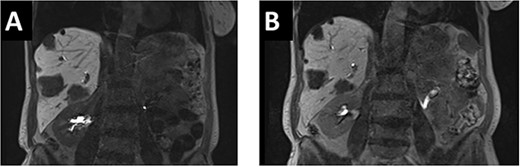

After multidisciplinary tumor board (MDT) discussion, neoadjuvant chemotherapy with six cycles of FOLFOXIRI and Bevacizumab followed by liver-first approach was decided. Restaging after 3 months showed stable disease of the CRLM, therefore, chemotherapy was continued. After 12 cycles, restaging revealed a size reduction of 12% of the CRLM (Fig. 1B). CEA decreased from 69 to 6.1 ug/l. The patient was then admitted to our department for the evaluation of a curative intent CRLM resection. The radiological work-up revealed three remaining metastases on the left- and seven on the right hemiliver. Volumetry illustrated a standardized FLR (sFLR) for a right hemihepatectomy of 30%. In an MDT and the patient was deemed amenable to ALPPS surgery due to the marginal sFLR, bilobar metastases and exceptionally good performance status. Preoperative liver function tests showed normal liver function (LiMAx 450 mcg/kg/h, cut-off >315 mcg/kg/h and ICG R15: 4.0%, cutoff <12%). Although liver biopsy is not routinely performed before ALPPS, MDT recommended a biopsy of the healthy liver to rule out chemotherapy-associated steatohepatitis after 12 cycles of FOLFOXIRI and Bevacizumab in order to ensure a safe liver resection. The biopsy showed signs of subacute hepatocyte demise without fibrosis or cirrhosis. The day after the liver biopsy, the patient collapsed and was admitted to the emergency department of another hospital. CT scan showed a large intrahepatic hematoma (Fig. 2) without active bleeding probably secondary to the biopsy procedure. Due to a hemoglobin drop of 12 g/l a day later and the enlargement of the hematoma in follow-up CT scan, the patient was admitted to angiography, which showed several subcapsular liver bleedings, therefore the right hepatic artery was embolized. Luckily, an accessory right hepatic artery arising from the superior mesenteric artery was present. This enabled us to stay on track with the ALPPS procedure as the right hemiliver would be otherwise without any blood supply (Fig. 3). In synopsis of those findings, the operation was scheduled.

(A/B) CT-scan showing a large intrahepatic hematoma after liver biopsy on the right side.